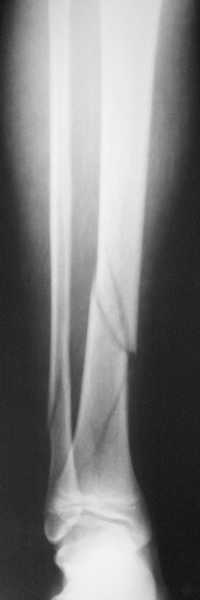

Уважаемый Иван! Если есть ЭОП, то перелом подходит для малоинвазивной

фиксации. Репозиция суставного отдела (использовать репозиционные

щипцы)и его фиксация стягивающими винтами чрезкожно, затем пластина

медиально малоинвазивно, лучше метафизарная. Если не располагаете

подходящим имплантом или непозволяют мягкие ткани, вполне возможно

применить вместо платы Fix.Ex. В приложении метафизарный перелом у

ребёнка 14лет, с распространением линии перелома на зону роста.